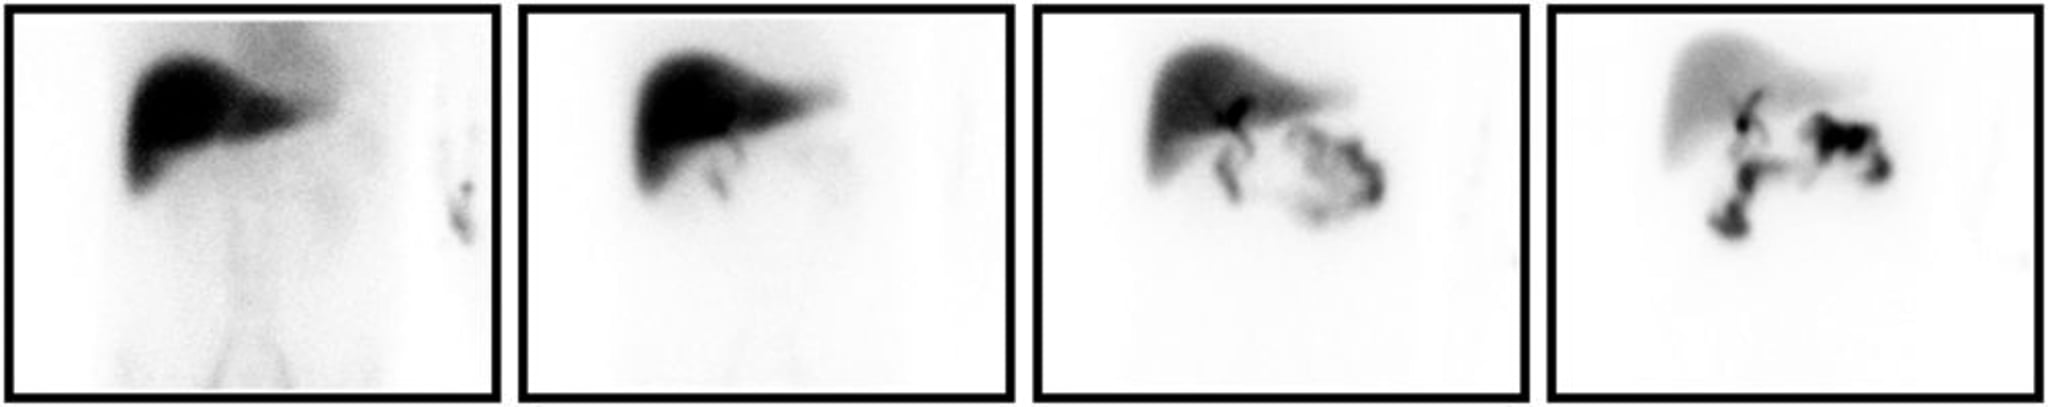

Scintigrafia con acido idrossiminodiacetico

Scintigrafia con acido idrossiminodiacetico coerente con diagnosi di colecistite. Da sinistra a destra, le immagini acquisite a 5, 15, 30 e 60 minuti dopo l'iniezione di radiotracciante. Anche in controlli successivi, non c'è riempimento della colecisti.